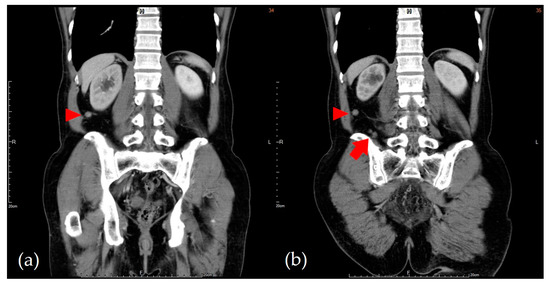

2. Case Presentation